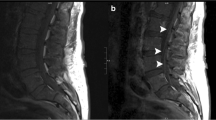

Based on the risk profile, additional diagnostic tests such as EEG, electrophysiological examinations, or cerebral/spinal imaging may be required to classify pathological findings during or after the treatment cycle or to take specific preventive measures before the initiation of therapy, like an adjustment of dosage of anti-seizure medication. In case of acute neurological complications, close interdisciplinary cooperation should be guaranteed, enabling to conduct targeted diagnostics. At the end of the hospital stay, a neurological final examination with recommendations for further outpatient treatment, e.g., regarding physiotherapy or medication adjustment, can contribute to advance recovery of oncological patients, resulting in an improvement of their quality of lives. Figure 3, which can be find at the end of this section, illustrates an exemplary patient pathway for neurological monitoring during CAR T-cell therapy, which serves both patient care and scientific inquiries.

Example 1: A patient with advanced lymphoma presents for CAR T-cell therapy. In addition to structural epilepsy after stroke, the patient has developed a length-dependent peripheral neuropathy due to several chemotherapy cycles as well as cognitive and amnestic deficits that impair daily life. In the inpatient setting, the patient undergoes a general neurological baseline examination, a neuropsychological testing, a cerebral MRI, NfL determination, and an EEG, on the basis of which the seizure-suppressing medication is administered prior to CAR T-cell therapy. Seven days after CAR T-cell therapy, the patient develops severe ICANS with recurrent epileptic seizures. MRI shows a mild ubiquitous barrier disturbance without any other changes from the initial findings. In addition, there is a significant increase in NfL. After ruling out all relevant neurological differential diagnoses, high-dose methylprednisolone therapy is initiated immediately. The seizures cease with a readjustment of the seizure-suppressing medication. Regular neurological follow-up examinations show rapid improvement of symptoms. The mild sensorimotor hemiparesis can be classified as pre-existing based on findings of baseline examination. Due to ongoing fine motor impairment and tremor symptoms, a neurological rehabilitation measure is initiated. However, the patient is readmitted 1 week after discharge with suspected biphasic ICANS. A comparison of the neurological findings cannot objectively confirm any neurological deterioration, and the neurofilament has returned to its baseline level prior to CAR T-cell therapy. After ruling out infectious or metabolic complications, the patient is diagnosed with suspected chronic fatigue syndrome, and rehabilitation measure can be continued. Three months later, the patient presents for clinical follow-up in the neuro-oncological outpatient clinic. A described deterioration in memory function can be objectively verified by neuropsychological testing. However, the testing also suggests possible causal depression. Under antidepressant medication, the patient’s memory function stabilizes over time which can be confirmed by the further neuropsychological examinations.